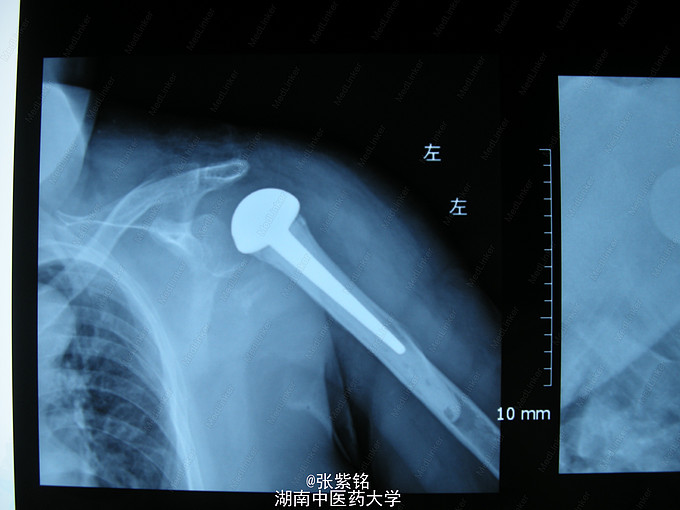

查体见:左额部可见约2cm*2cm皮下血肿,并可见一不规则伤口约2cm,伴活动性出血。脊柱驼背畸形,胸椎后凸,头部前伸体态;颈、腰部旋转活动不能,腰部于L3-5椎体棘突处压痛明显,双下肢肌力、肌张力正常。左肩部关节明显肿胀,可扪及空虚感;局部压痛明显,左Dugas征阳性,左肩关节主动上举,外展,后伸,内收活动受限;被动活动患处疼痛加剧,左侧桡动脉搏动可扪及,皮肤感觉正常,左肘、腕及各指间关节血运感觉活动正常。 X线片示:左肩关节脱位,左肱骨外科颈骨折,左肱骨大结节撕脱性骨折。

1、左肩关节脱位伴大结节撕脱性骨折,2、左肱骨外科颈骨折,3、头部外伤、头面部皮肤裂伤,4、强直性脊柱炎。 1、清创缝合伤口。2、患肢制动,消肿,止痛等对症处理。3、完善相关检查。4、择期行手术治疗及术后对症处理。